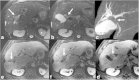

Malignancies of the biliary tract include cholangiocarcinoma, gallbladder cancers and carcinoma of the ampulla of Vater. Biliary tract adenocarcinomas are the second most common primary hepatobiliary cancer. Due to their slow growing nature, non-specific and late symptomatology, these malignancies are often diagnosed in advanced stages with poor prognosis. Apart from incidental discovery of gall bladder carcinoma upon cholecystectomy, early stage biliary tract cancers are now detected with computed tomography (CT) and magnetic resonance imaging (MRI) with magnetic resonance cholangiopancreatography (MRCP). Accurate characterization and staging of these indolent cancers will determine outcome as majority of the patients' are inoperable at the time of presentation. Ultrasound is useful for initial evaluation of the biliary tract and gallbladder masses and in determining the next suitable modality for further evaluation. Multimodality imaging plays an integral role in the management of the biliary tract malignancies. The imaging techniques most useful are MRI with MRCP, endoscopic retrograde cholangiopancreatography (ERCP), endoscopic ultrasound (EUS) and positron emission tomography (PET). In this review we will discuss epidemiology and the role of imaging in detection, characterization and management of the biliary tract malignancies under the three broad categories of cholangiocarcinomas (intra- and extrahepatic), gallbladder cancers and ampullary carcinomas.